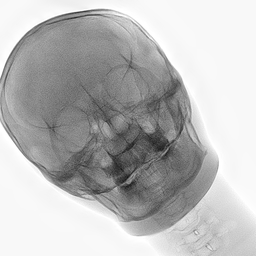

Table 2: Comparison of style transfer outputs across the five methods. All the outputs are derived from the synthetic inputs.

Synthetic Closest Real Hierarchy Flow (st=0.25) CycleGAN (ss=0.0) Z-STAR SDEdit (st=0.2) MedShift (τ\boldsymbol{\tau}=0.45)

As shown in Table 3, CycleGAN-Turbo achieves the strongest performance on distributional metrics such as CFID and density, but this comes at the cost of anatomical fidelity. The implementation of the structural similarity loss did not yield the expected outcomes. The qualitative results in Table 2 reveal that it introduces spurious features, especially in the second row, undermining structural correctness. In contrast, Hierarchy Flow preserves anatomical details exceptionally well by applying minimal transformation, resulting in outputs that closely resemble the input and thus offer limited to no domain adaptation. As noted in Figure 3 and Table 3, the model completely breaks down at high style strengths values without improvement in FID.

MedShift is evaluated in three τ\tau settings to explore the trade-off between structural preservation and generative realism. At τ=0.6\tau=0.6, the model is second only to HierarchyFlow in maintaining structure, while significantly outperforming it in CFID and coverage. The low-fidelity setting (τ=0.3\tau=0.3) reaches CFID values comparable to CycleGAN but with far fewer anatomical distortions. The intermediate configuration (τ=0.45\tau=0.45) provides a good trade-off, as seen in Table 2. Z-STAR maintains structure but fails to transfer style effectively to the lower jaw, while SDEdit captures pixel intensities well but introduces artifacts into the cranial region, particularly in the second example. As shown in Figure 3, MedShift achieves a more favorable balance between structural fidelity and image realism across all τ\tau settings, outperforming the other models in this trade-off space. This reinforces the findings based on average ranking, confirming MedShift as the most well-rounded strategy.